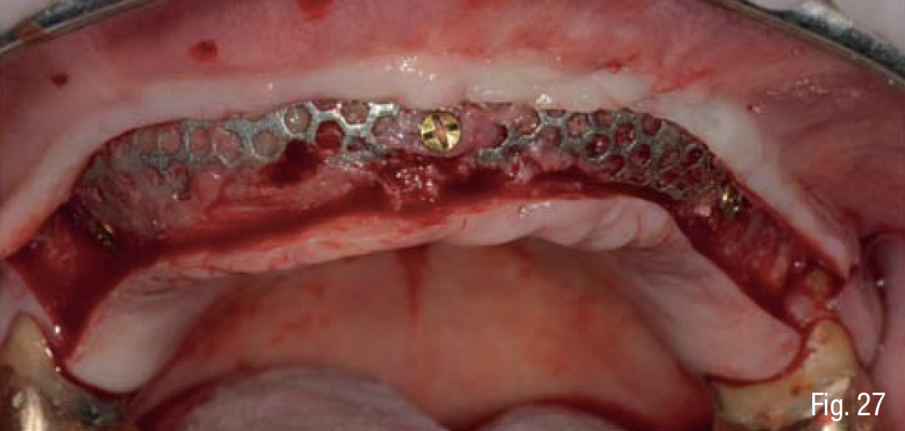

Durante la fase di chirurgia implantare, è stata inizialmente fissata la dima chirurgica sfruttando l’appoggio dento-mucoso; successivamente, è stata eseguita un’incisione lineare crestale e si è proceduto al sollevamento di un lembo vestibolare a tutto spessore e alla rimozione delle mini-viti e della griglia, che essendo osteointegrata in diversi punti è stata rimossa in diversi frammenti. La percentuale di rigenerazione, ovvero il rapporto tra il volume osseo rigenerato e il volume osseo pianificato, è stato calcolato essere del 96% (Figg. 25-29). La dima chirurgica è stata riposizionata e fissata nuovamente mediante i pin di fissaggio precedente preparati, non avendo più il supporto mucoso. Usando una tecnica di sotto-preparazione, sono stati realizzati i siti implantari e sono poi stati inseriti i 6 impianti programmati: 4 impianti dritti con dimensione 10 x 3.7 mm e 2 impianti angolati a 25° con dimensione 12 x 3.7 mm, al fine di evitare il seno mascellare (BTK implant Isy+, Biotec Srl, Dueville, Vicenza, Italy) (Fig. 30).